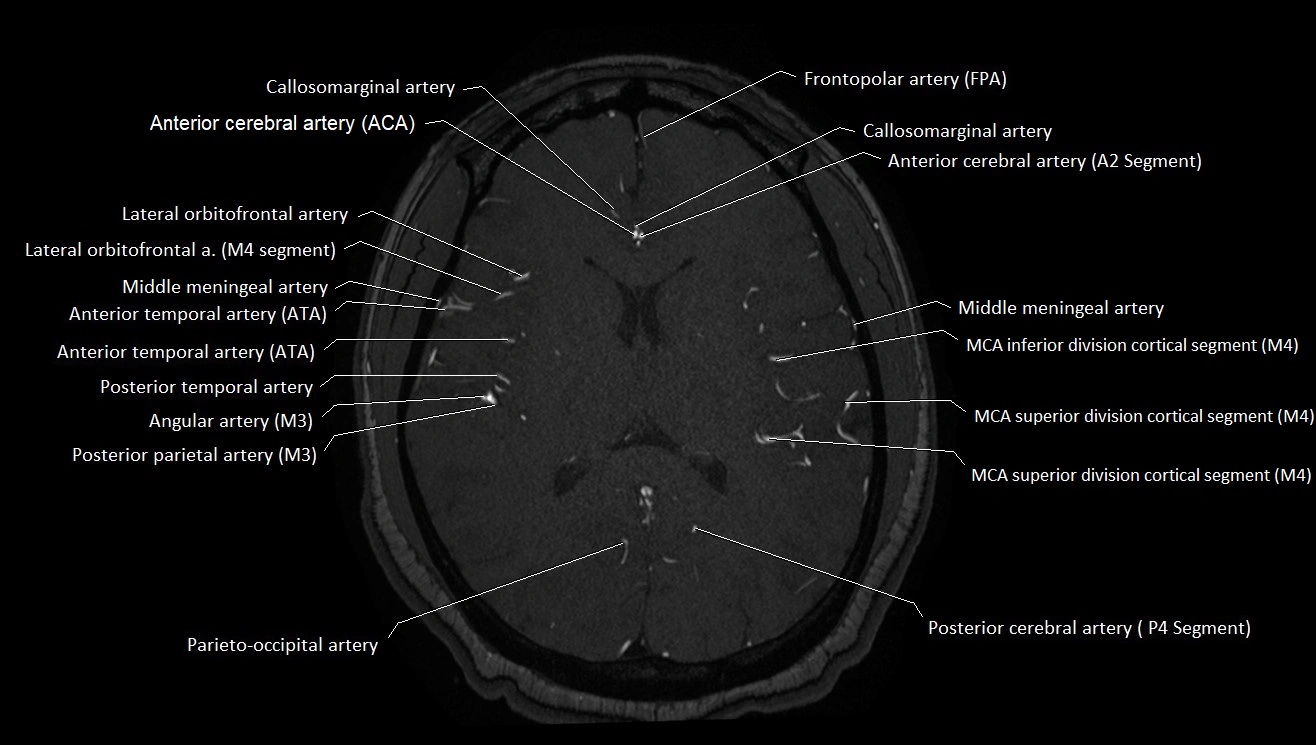

MRI Appearance

T1-weighted images:

• Vessel appears as a flow void (dark lumen) near the optic tract and temporal horn

• Surrounding parenchyma intermediate signal

T2-weighted images:

• Vessel lumen shows dark flow void

• Ischemic infarcts in its territory (internal capsule, thalamus) appear hyperintense

FLAIR:

• Vessel not seen directly; infarcts in AChA territory appear as hyperintense cortical/subcortical changes

• Chronic infarcts show gliotic hyperintensity

MRA (Magnetic Resonance Angiography):

• Flow-related enhancement makes the AChA appear as a bright, linear vascular signal against suppressed background

• High sensitivity for origin and proximal course; distal branches may be too small to resolve

• Detects stenosis, occlusion, aneurysm, AVM feeders